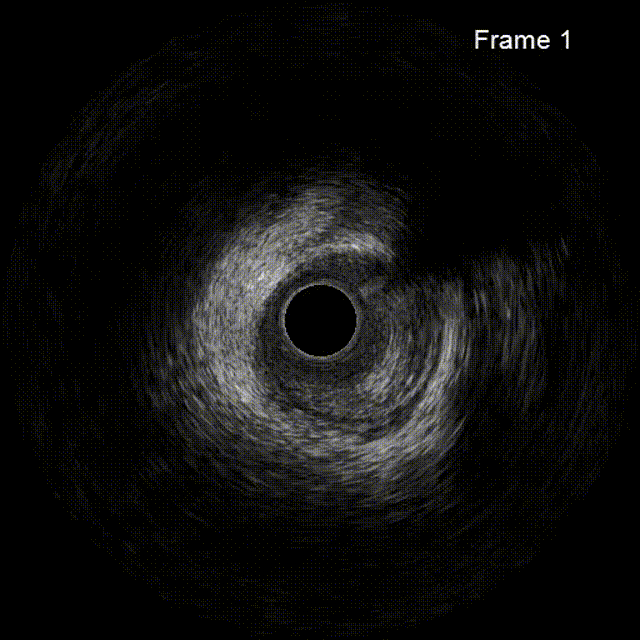

右冠术前术后IVUS图像